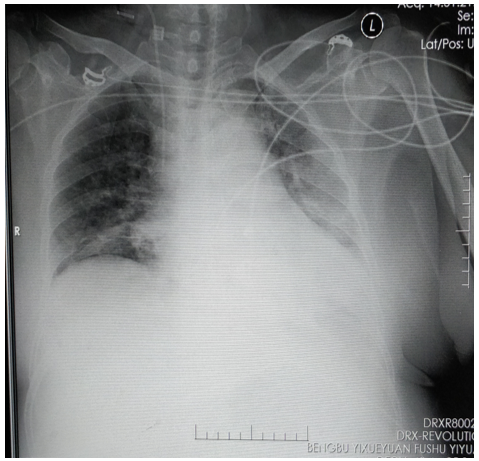

床旁胸片:左肺炎性病变;左下肺不张,左侧胸腔积液(图3)

图片

图3  患者入我科后床旁胸片